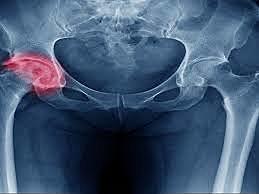

• Primer reemplazo de cadera

Primer reemplazo de cadera

Se realiza el primer reemplazo de cadera.